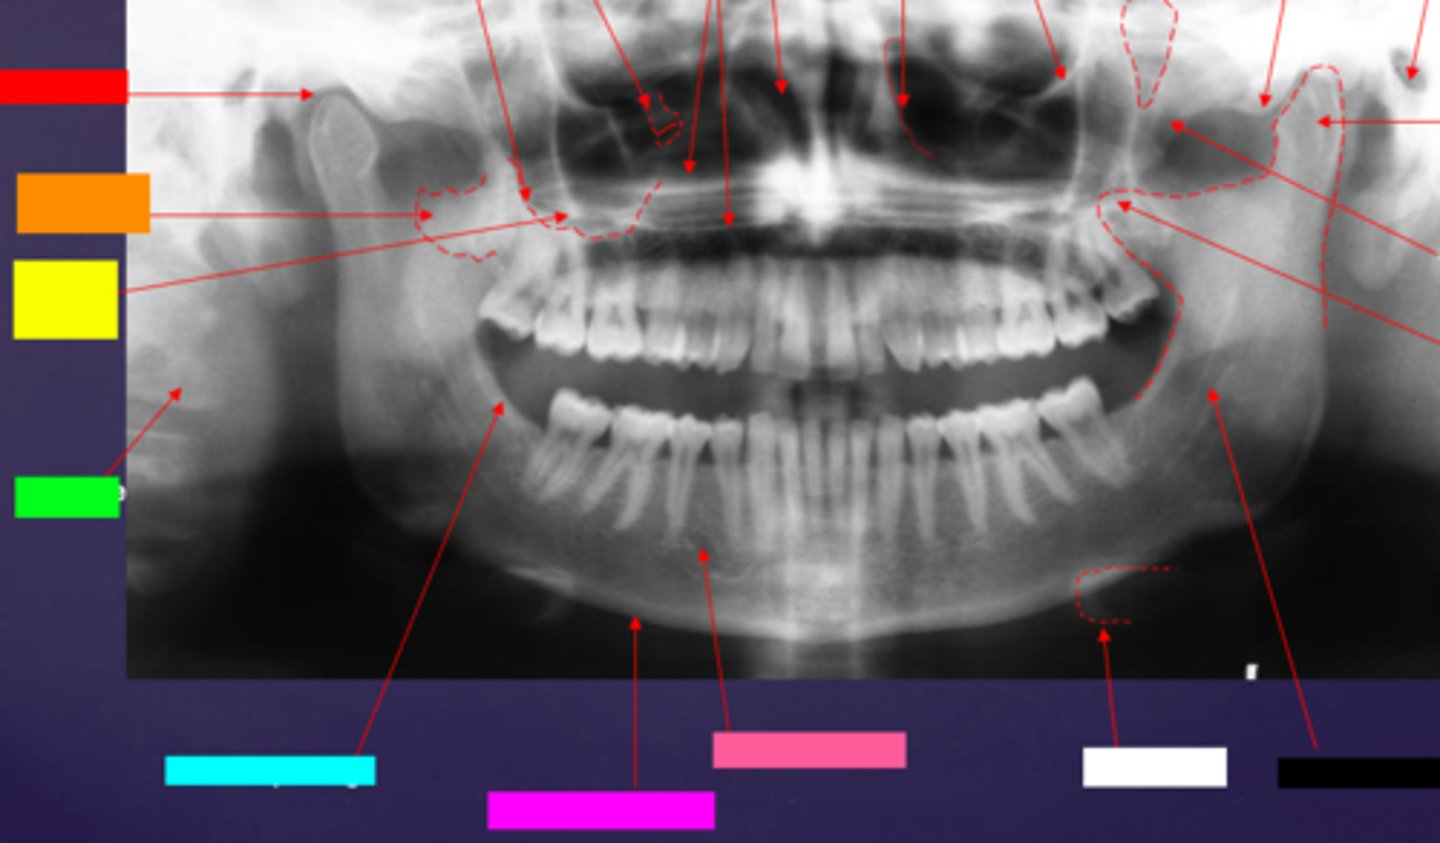

ID the soft tissue anatomy indicated by the arrow pointing from the red box:

posterior pharyngeal wall

ID the soft tissue anatomy indicated by the arrow pointing from the orange box:

soft palate

ID the soft tissue anatomy indicated by the arrow pointing from the yellow box:

dorsal surface of tongue

ID the soft tissue anatomy indicated by the arrow pointing from the green box:

middle nasal meatus

ID the soft tissue anatomy indicated by the arrow pointing from the light blue box:

inferior nasal meatus

ID the soft tissue anatomy indicated by the arrow pointing from the hot pink box:

inferior nasal concha (turbinate)

ID the soft tissue anatomy indicated by the arrow pointing from the brown box:

upper lip

ID the soft tissue anatomy indicated by the arrow pointing from the white box:

lower lip

ID the soft tissue anatomy indicated by the arrow pointing from the grey box:

ghost image of opposite mandible